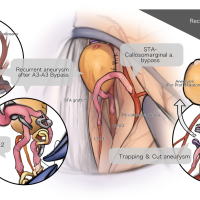

術後イラストシリーズ

脳神経外科速報 増刊号 基本手技のバリエーション(メディカ出版) 寄稿シリーズ